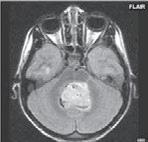

Zobrazení

D-W malformace je charakterizována hypoplazií vermis mozečku, rozšířením IV. mozkové komory, která se často cysticky vyklenuje dorzálně a může imitovat arachnoidální cystu, rozšířením zadní jámy lební a vysokým úponem tentoria s confluens sinum nad lambdovým švem. Okcipitální kost může být vlivem tlakových změn remodelována, existují i případy s porušením její kontinuity a encefalokélou. Hydrocefalus pozorujeme v 80 %, častá je přítomnost dysgeneze corpus callosum, schizencefalie.

D-W variant byl vyčleněn pro případy, kdy všechny základní příznaky nemusí být plně vyjádřeny nebo může některý zcela chybět. Bývá přítomna hypoplazie mozečku, což je dominantní příznak, IV. komora je obvykle rozšířena, někdy pozorujeme, že tvarem připomíná na axiální řezu „klíčovou dírku“, zadní jáma lební naopak rozšířena nebývá.

Obr. I.1.8a Dandy-Walkerova malformace, rozšířená IV komora (tvar klíčové dírky)

Obr. I.1.8b Dandy-Walkerova malformace, rozšířená IV komora široce komunikující s cisterna magna, hypotrofie mozečku (snímky zapůjčeny z archivu prim doc MUDr M Mechla, Ph D, MBA)

Obr. I.1.8c Dandy-Walkerova malformace, rozšířená IV komora široce komunikující s cisterna magna, hypotrofie mozečku (snímky zapůjčeny z archivu prim doc MUDr M Mechla, Ph D, MBA); stejný pacient jako na obr I 1 8b

Obr. I.1.8d Dandy-Walkerova malformace, rozšířená IV komora široce komunikující s cisterna magna, hypotrofie mozečku, vysoký úpon tentoria (šipka) (snímky zapůjčeny z archivu prim doc MUDr M Mechla, Ph D, MBA); stejný pacient jako na obr I 1 8b, c

Obr. I.1.8e Dandy-Walkerovo spektrum (hypoplazie vermis, IV komora je rozšířená a široce zeje) (snímky zapůjčeny z archivu as MUDr J Lisého, CSc )

Obr. I.1.8f Dandy-Walkerovo spektrum (hypoplazie vermis, IV komora je rozšířená a široce zeje) (snímky zapůjčeny z archivu as MUDr J Lisého, CSc ); stejný pacient jako na obr I 1 8e

Obr. I.1.8g Dandy-Walkerovo spektrum (hypoplazie vermis, IV komora je rozšířená a široce zeje), (snímky zapůjčeny z archivu as MUDr J Lisého, CSc ); stejný pacient jako na obr I 1 8e, f